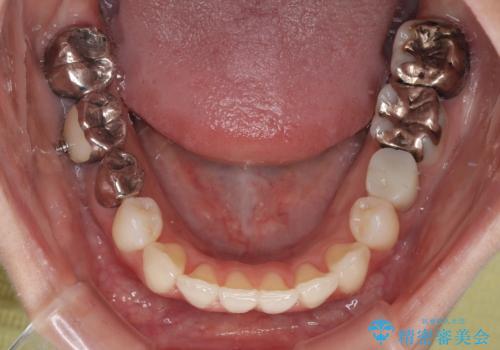

- 上下前歯のデコボコとクロスバイトを気にして来院された患者様です。

治療済みの処置歯が多いため、インビザラインを用いて矯正治療を行うこととしました。

下顎臼歯部にブリッジが装着されており、移動不可のため、IPR(歯と歯の間を削る)と歯列全体を拡大させることで、歯並びを整えていくこととしました。

インビザライン特有の奥歯の噛みにくさが治療後半に発現しましたが、無事に終了させることができました。